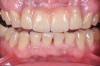

Fig 5. Preoperative view of patient requiring esthetic changes up to at least the bicuspids (Fig 5); postoperative view with CL-I feldspathic porcelain veneers up to the first bicuspid (Fig 6).

Figure 5

Fig 6. Preoperative view of patient requiring esthetic changes up to at least the bicuspids (Fig 5); postoperative view with CL-I feldspathic porcelain veneers up to the first bicuspid (Fig 6).

Figure 6